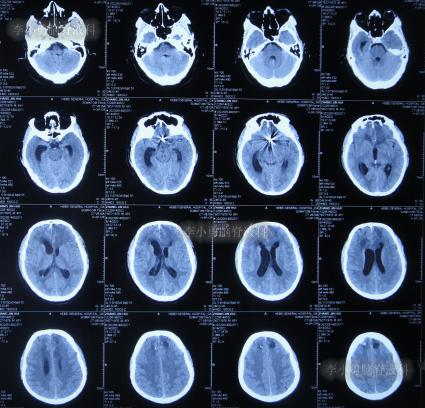

该院治疗20余天时间内,虽每天进行腰穿治疗,但期间3次查头颅CT均显示脑室持续的扩张(图-7、图-8、图-9)。

图-7:2022年8月9日头颅CT

图-8:2022年8月14日头颅CT

图-9:2022年8月15日头颅CT